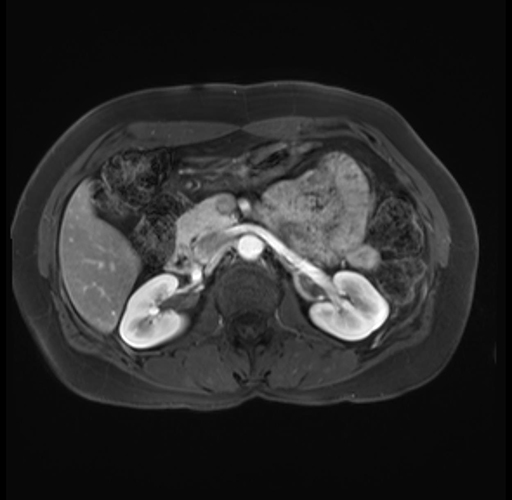

Imaging Analysis

Look through the patient's CT scan to identify any areas of concern for the necessary procedure.

Based on your CT findings, which issue(s) are present and would give reason for "planned slowing down moment(s)" in this case?

Considering a standard distal pancreatectomy procedure, what step(s) of the operation would you do differently in this case?